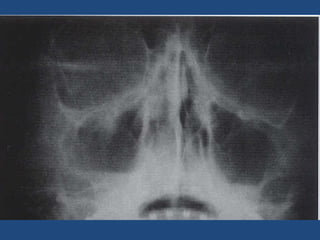

Diagnostic Strategies Midface or maxillary  fractures: Water’s or occipitomental veiw (stable patient). CT scan if: +ve plain x-ray , unstable patients and complex fractures. ( corononal and sagittal or 3 dimension reconstruction) Mandible injuries: Panorex radiographs. Coronal CT for condyle fractures.

Zygoma Tripod Fractures Imaging Studies Radiographic imaging: Waters, Submental and Caldwell views Coronal CT of the facial bones: 3-D reconstruction

Zygoma Tripod FracturesImaging Studies Radiographic imaging: Waters, Submental and Caldwell views Coronal CT of the facial bones: 3-D reconstruction

• #30 Plain films including the waters, submental and caldwell views. Can demonstrate the fracture and evaluate the zygomaticomaxillary complex, but a Coronal CT of the facial bones will best show involvement and the degree of displacement. Picture: CT 3-D. The fracture lines involved in a tripod fracture are demonstrated in this 3-D reconstruction.